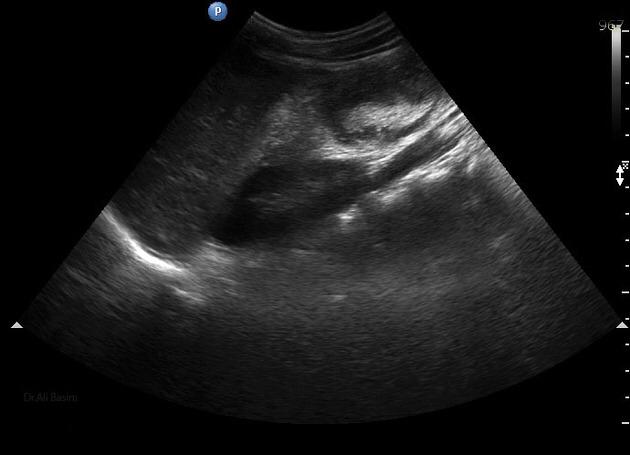

Ultrasonido de Glándula Tiroides

El término nódulo tiroideo se refiere a cualquier crecimiento anormal de las células tiroideas que forman un tumor dentro de la tiroides. Aunque la gran mayoría de los nódulos tiroideos son benignos (no cancerosos), una pequeña proporción de estos nódulos sí...